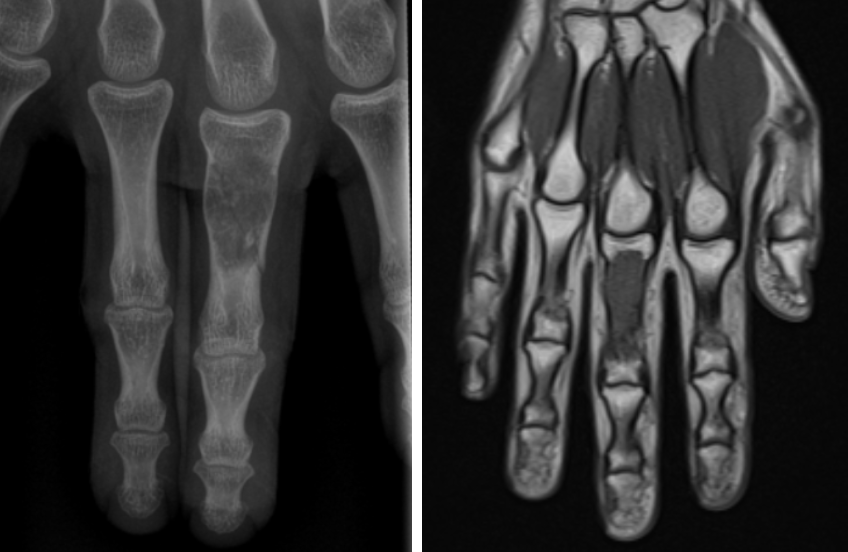

주로 X-ray(단순 방사선 검사)로 진단하며, 필요에 따라 CT, MRI 등 추가 영상 검사가 사용됩니다.

악성 여부가 의심되면 골생검이 필요할 수 있습니다.